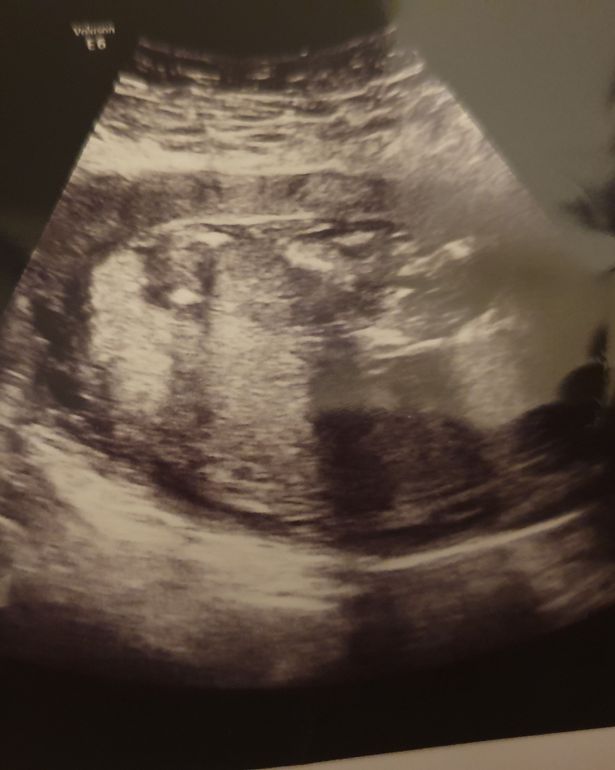

据《镜报》12月9日报道,英国德比郡一名女子怀孕仅13周羊水就破了,但是她坚持拒绝中止妊娠。在她怀孕29周后,她成功地生下了一名女婴。令人震惊的是,孩子奇迹般地活了下来,医生曾一度警告称,这个孩子会是个死胎。

23岁的柯斯蒂·米宗(Kirsty Mizon)在怀孕13周时羊水就破了。医生不断告诉柯斯蒂,孩子会胎死腹中。柯斯蒂甚至已经准备好了葬礼。然而,最终孩子顺利地出生了。

“医院的医生说我羊水破了,我的孩子将在48小时内在肚子里去世。他们让我回家,等着孩子出生。我崩溃地回到家。但我并没有生下死胎,我孩子的心仍然砰砰地跳着。”

科斯蒂的孩子只有百分之一的存活几率,因此医生一直要求她终止妊娠。并且,就算孩子活下来,小女孩可能也将会是严重残疾。

柯斯蒂原本计划在怀孕34周时进行剖腹产,但29周时她开始感到疼痛并早产。